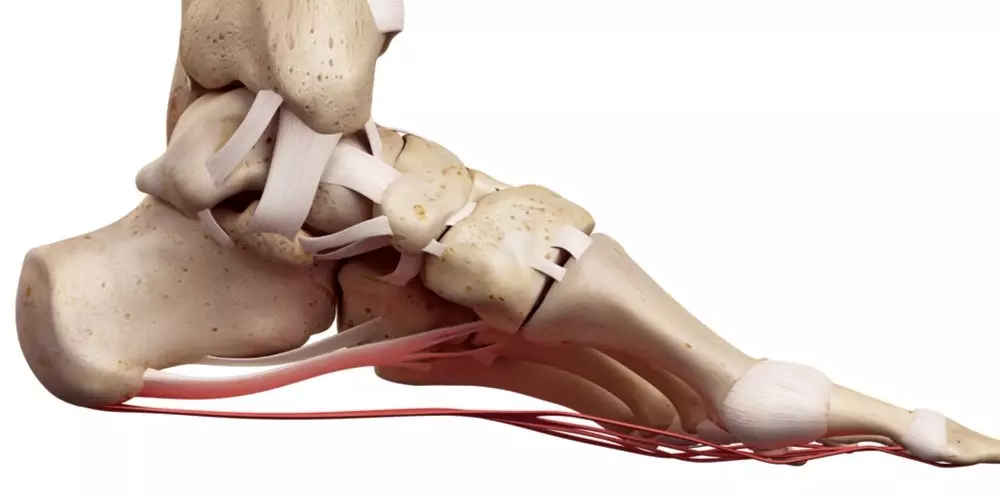

Przykurcz Dupuytrena jest bliźniaczy dla choroby Ledderhose’a, czyli włókniakowatości guzowatej rozcięgna podeszwowego. Ta „polega na tworzeniu się twardych guzowatych zwłóknień w obrębie rozcięgna podeszwowego stopy. Pod skórą w okolicy łuku podłużnego zaczynają powstawać twarde, często powodujące dyskomfort, a czasem nawet i ból, guzki o średnicy sięgającej kilku centymetrów”. Może ona początkowo nie dawać objawów, dopiero z czasem przechodząc w fazę objawową, w której pojawia się utrata elastyczności rozcięgna podeszwowego oraz przykurczu. Jest to choroba rzadsza niż przykurcz Dupuytrena, jednak mogą one występować razem.